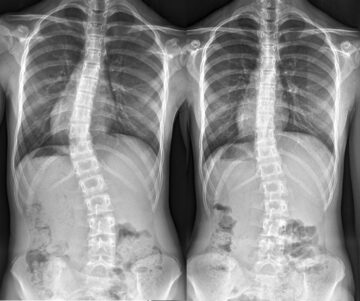

اعوجاج العمود الفقري عند الأطفال والمراهقين والبالغين: دليل شامل للعلاج حسب السن يعاني الكثير من الأطفال والمراهقين وحتى البالغين من اعوجاج العمود الفقري، وهو ميلان غير طبيعي للعمود الفقري يمكن أن يظهر على شكل

الجنف التنكسي عند البالغين: أسبابه وأعراضه وأفضل طرق العلاج الجنف التنكسي، أو ما يُعرف أيضًا باسم “الجنف التنكسي لدى البالغين”، هو حالة طبية تظهر نتيجة تآكل أو تدهور في فقرات العمود الفقري مع التقدم